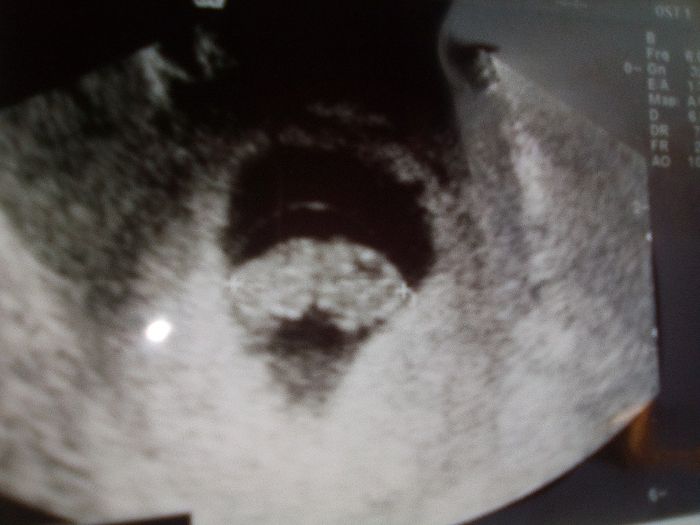

Ciaooo qualcuna ha sentito parlare del metodo Ramzi? A voi ci ha azzeccato o ha sbagliato? Vi metto una foto dellβeco interna a 7+3 βdovrebbeβ essere maschio secondo la...